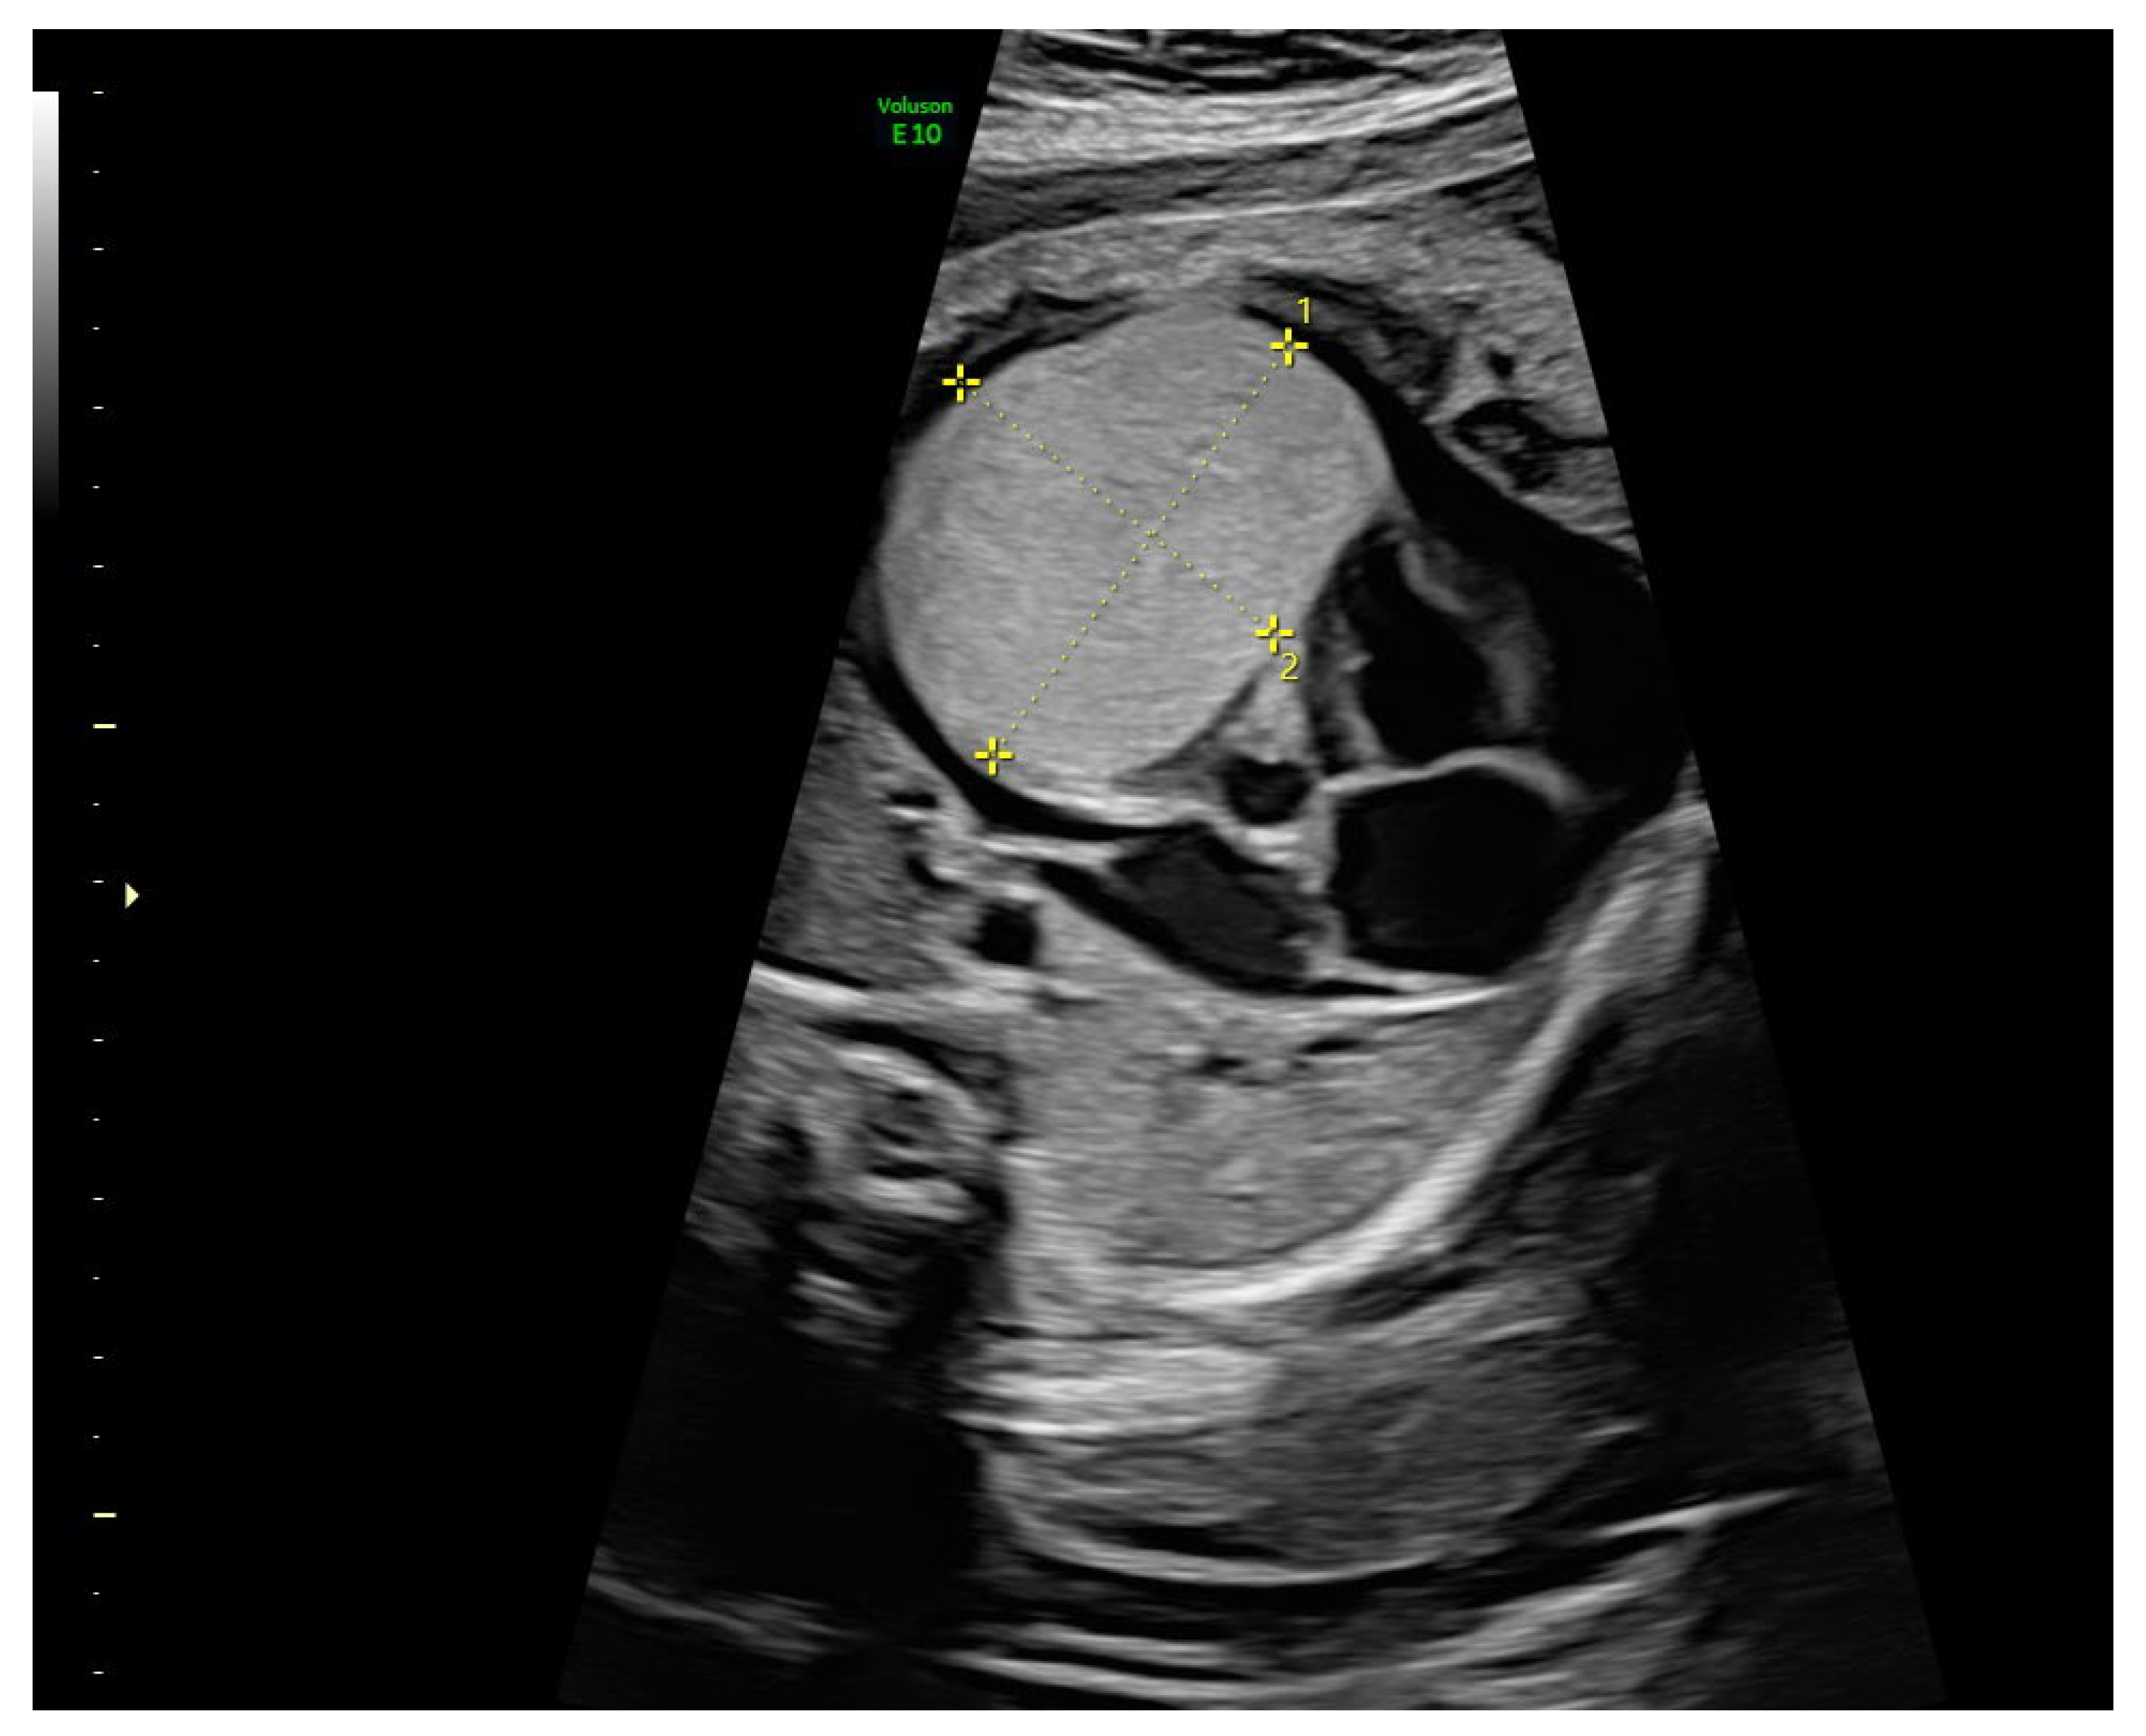

2. Case